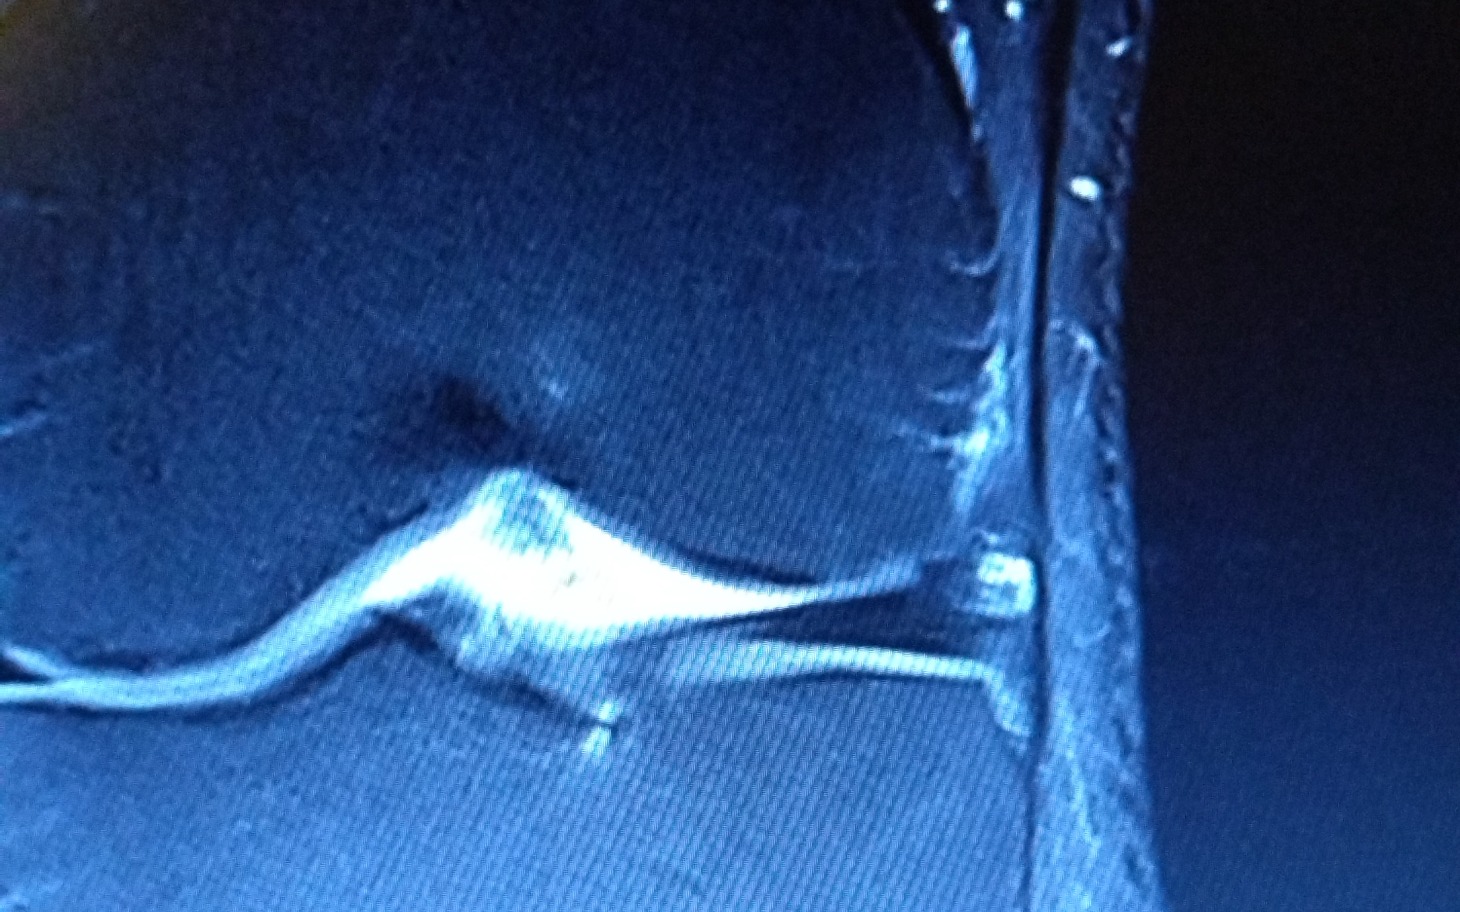

Niespełna miesiąc temu, miałem wypadek. Na pierwszy rzut oka wydawało by się że nic poważnego, zwykły upadek na kolano z nie dużej wysokości. Jednak objawy i ból sugerowały że jednak to coś poważniejszego. Zrobiłem USG które wykazało jakieś zmiany ale potrzebna była dalsza diagnostyka. Po zrobieniu rezonansu magnetycznego przyszedł czas na diagnozę i pierwsze niedowierzanie. Naderwane więzadło krzyżowe przednie i tylne, pęknięta łąkotka przyśrodkowa, złamana rzepka i oderwany kawałek chrząstki stawowej. Po pierwszym szoku że z takiego wydawało by się nie groźnego upadku może wyjść coś tak poważnego, przyszedł czas na drugi.